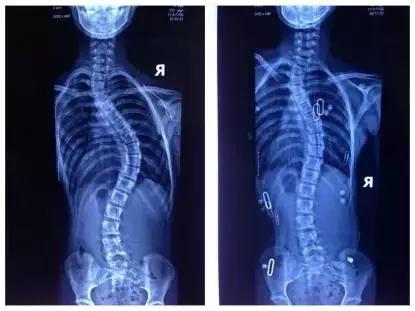

以下X片显示了带支具前后的角度变化:

左边为佩戴支具后:度数从55度降低到35度